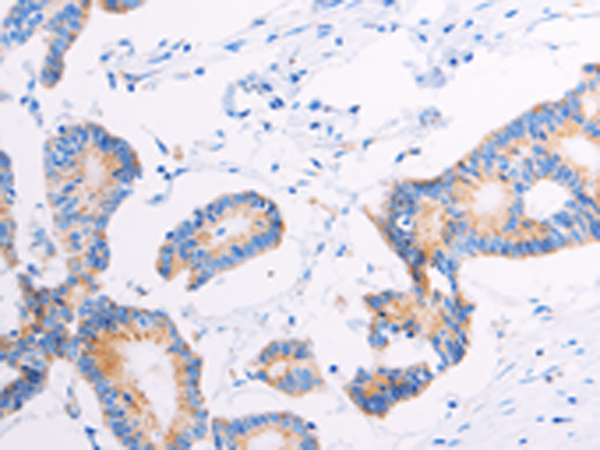

分类: 科研抗体货号: P04275别名: GCAP; ALPPL; ALPPL2应用: IHC反应种属: Human